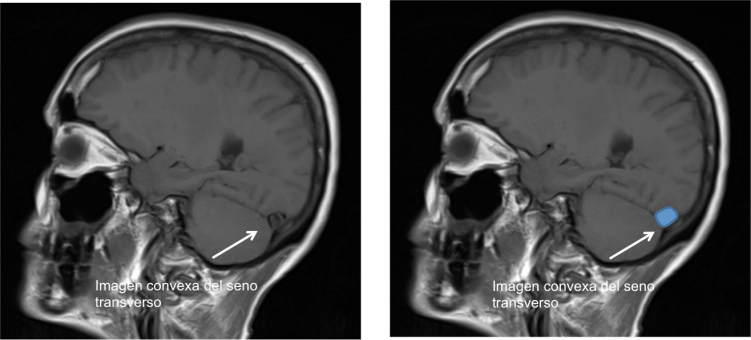

En la Imagen 4 y 5 podemos ver el aspecto congestivo y redondeado de los senos venosos longitudinal y transverso.

En la Imagen 8, podéis observar el signo de distensión venosa descrito en casos de hipotensión intracraneal que se refiere a un cambio de la morfología del margen inferior de la porción media del seno transverso que adquiere una morfología convexa.